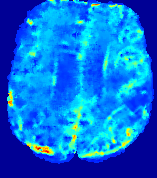

LesionRefer to captionRefer to captionRefer to captionRefer to captionRefer to captionRefer to caption𝐕rgbsubscript𝐕𝑟𝑔𝑏{\bf{V}}_{rgb}Refer to captionRefer to captionRefer to captionRefer to captionRefer to captionRefer to caption𝐕2subscriptnorm𝐕2{\|\bf{V}}\|_{2}Refer to captionRefer to captionRefer to captionRefer to captionRefer to captionRefer to captionRefer to caption3.53.53.52.82.82.82.12.12.11.41.41.40.70.70.70.00.00.0(mm/s)𝑚𝑚𝑠(mm/s)D𝐷DRefer to captionRefer to captionRefer to captionRefer to captionRefer to captionRefer to captionRefer to caption0.0200.0200.0200.0160.0160.0160.0120.0120.0120.0080.0080.0080.0040.0040.0040.0000.0000.000(mm2/s)𝑚superscript𝑚2𝑠(mm^{2}/s)Slice #1Slice #2Slice #3Slice #4Slice #5Slice #6

Figure 3: PIANO feature maps for one stroke patient, where the lesion is located in the left hemisphere. Top row: segmented stroke lesion region (white) on different slices, obtained from ISLES 2017. The corresponding slices for the PIANO feature maps are shown in the following rows.

For a better insight into an estimated velocity field 𝐕𝐕{\bf{V}} and diffusion field 𝐃𝐃{\bf{D}}, we compute the following maps: (1) 𝐕rgbsubscript𝐕𝑟𝑔𝑏{\bf{V}}_{rgb}: Color-coded orientation map of 𝐕=(Vx,Vy,Vz)T𝐕superscriptsuperscript𝑉𝑥superscript𝑉𝑦superscript𝑉𝑧𝑇{\bf{V}}=(V^{x},V^{y},V^{z})^{T}, obtained by normalizing 𝐕𝐕{\bf{V}} to unit length and mapping its 3 components to red, green, blue respectively; (2) 𝐕2subscriptnorm𝐕2\|{\bf{V}}\|_{2}: 222 norm of 𝐕𝐕{\bf{V}}; (3) D𝐷D: scalar field in Eq. 5.

Fig. 3 and Fig. 4 show the PIANO feature maps estimated from two ISLES 2017 patients: all are highly consistent with the lesion in both cases. Details of the blood flow trajectories are revealed in 𝐕rgbsubscript𝐕𝑟𝑔𝑏{\bf{V}}_{rgb} by the ridged patterns and the sharp changes of colors in the unaffected (right) hemisphere, while the flat patterns appearing within the lesion provide little directional information about the velocity and indicate low velocity magnitudes. Velocity magnitudes are more directly visualized via 𝐕2subscriptnorm𝐕2\|{\bf{V}}\|_{2}, from which one can easily locate the lesion where 𝐕2subscriptnorm𝐕2\|{\bf{V}}\|_{2} is low. D𝐷D also indicates lower diffusion values in the lesion, though with less contrast potentially due to the fact that it captures the accumulated effect of CA diffusion at the voxel-level.